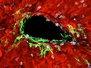

Image identification by machine learning models is a major application of artificial intelligence (AI). And, with ever-improving capabilities, the use of these models for medical diagnostics and research is becoming more commonplace. Doctors analysing X-rays and mammograms, for instance, are already being assisted by AI technology, and models trained to identify signs of disease in tissue sections are also being developed to help histopathologists. The models are trained with microscope images annotated by humans – the image, for example, shows a section of rat testis with signs of tubule atrophy (pale blue shapes) with other coloured shapes indicating normal tubules and structures. Once trained, the models are tasked with categorising unannotated datasets. The latest iteration of this technology was able to identify disease in testis, ovary, prostate and kidney samples with exceptional speed and high accuracy – in some cases finding signs of disease that even trained human pathologists had missed.